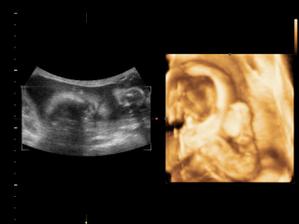

18.10.2010 Naše prďolka se konečně otočil a ukázel se. Pán doktor nám potvrdil,že to bude chlapeček. Nemůžeme si vybrat jméno. Pro holčičku bylo jasné,ale u chlapečka máme problém. Seznam se zůžil na 3 jména. Martin,Daniel a nebo Domink.

14.12.2010 (27tt+6)Nám pan doktor řekl,že Daneček je ukázkový, že má 1,076kg a má vše co má mít! 🙂